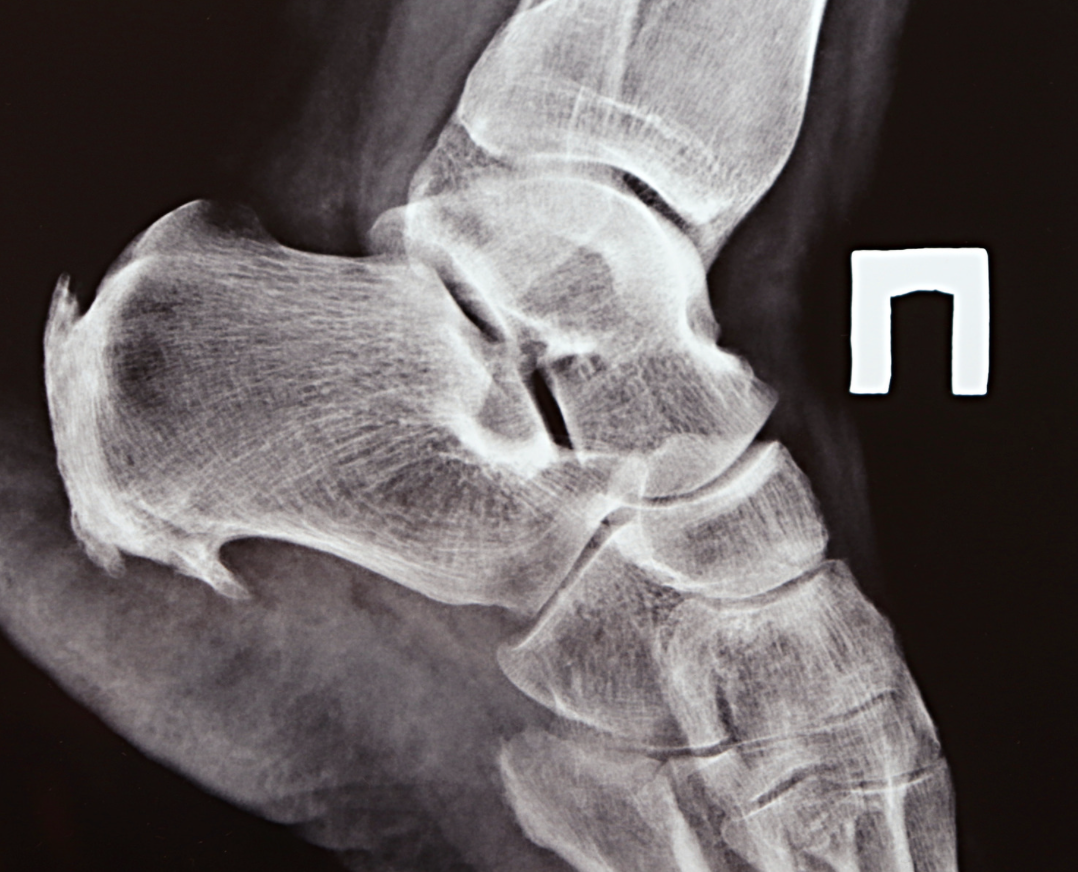

Пяточная шпора — воспаление подошвенной фасции. На месте постоянного напряжения формируется костный нарост, который давит на мягкие ткани при каждом шаге.